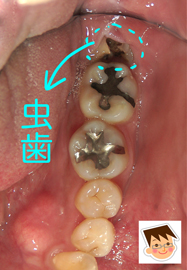

30代の男性。主訴は「親知らず辺りが、ズキズキ痛い。痛みをとって欲しい」

Dr:「横向きに生えている親知らずの一部が、奥の歯茎から見えています。そこが虫歯になっていますので、歯を抜く以外の選択はありません。虫歯が深く進行しているほど、抜歯は簡単ではなくなります。まずは、レントゲンを撮ってから、施術方法や抜歯後の症状などを詳しく説明します。